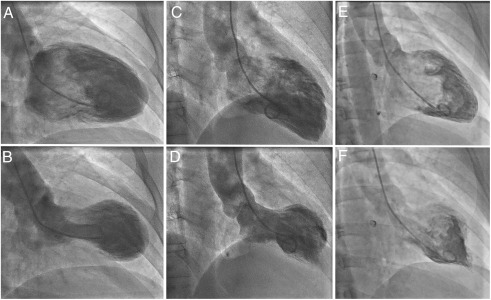

The term Takotsubo comes from Japanese and refers to a traditional octopus trap—Takotsubo pot—used by fishermen.

This pot has a round, narrow-necked shape, which closely resembles the appearance of the left ventricle in affected patients. During the acute phase of Takotsubon cardiomyopathy, the base of the heart contracts normally while the apex balloons outward, creating a silhouette strikingly similar to this vessel.

The condition was first described in Japan in the 1990s, and the name has remained due to this distinctive visual analogy.